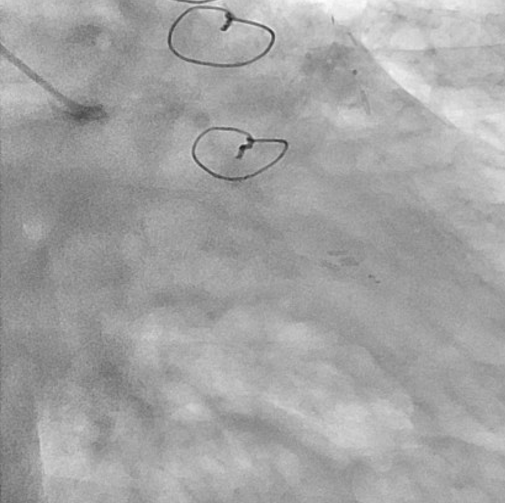

First, percutaneous coronary intervention (PCI) was performed toward the left anterior descending artery (LAD). The initial antegrade wire deviated from the true lumen; therefore, parallel wire technique was employed to achieve successful crossing. To avoid jailing the left circumflex artery (LCX) ostium, the stent was deployed precisely at the LAD ostium, and the left main trunk (LMT) was dilated using a 4.0-mm cutting balloon. One month later, intervention toward the LCX was undertaken. Intravascular ultrasound (IVUS) performed from the LAD confirmed achronic total occlusion (CTO) entry with a markedly thick plaque covering the LCX ostium. Although the lesion was accurately marked, penetration with a high-penetration guidewire was unsuccessful. Even with the balloon screen technique using a CP 8-20, wire penetration remained unsuccessful. Therefore, plaque debulking was selected to expose the CTO entry. Directional coronary atherectomy (DCA) was performed, and follow-up IVUS demonstrated significant plaquethinning compared with baseline. Subsequently, the CP 8-20 wire advanced smoothly, enabling successful wire crossing. The procedure was completed usinga mini-crush stenting strategy.